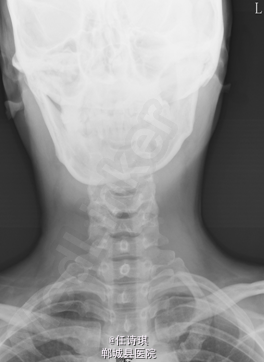

女,46岁8月,因“颈部不适3年,右上肢软弱疼痛伴双下肢胀痛1年”入院。3年前无明显诱因出现颈部不适,以局部胀痛为主,劳累后加重休息后可缓解,不伴上肢放射痛。遂未予特殊处理。1年前出现右上肢酸麻肿痛,以肘关节疼痛和手部皮肤麻木为主,行走约10分钟后自觉双小腿后侧胀痛,休息后可缓解。在当地医院诊断为“网球肘、颈椎病”予以对症治疗,但上述症状无明显改善。行MRI、CT等检查,诊断为“C2椎管内肿瘤”,未予特殊治疗。为求进一步诊断今日由门诊以“C2椎管内占位,性质?”收入院

专科查体:视:脊柱无明显畸形。触:颈胸部各棘突无明显压、叩痛。四肢肌张力正常,右手皮肤触觉减退。动量:右侧上肢肌力IV级,左侧肢体V级。右侧上肢腱反射活跃,双侧膝腱反射活跃,跟腱反射正常引出。Hoffman征阳性,Babinski征未引出。外院MRI示:C2椎管内脊髓背侧占位病变,脊膜瘤可能。T2椎体内异常信号,多为血管瘤。。

初步诊断:1、颈2节段椎管内占位伴不全四肢瘫(Frankel D):脊膜瘤?黄韧带骨化? 2、胸2椎血管瘤 处理:全麻下行经后路颈2全椎板切除、椎管探查减压、椎管内占位切除活检术,